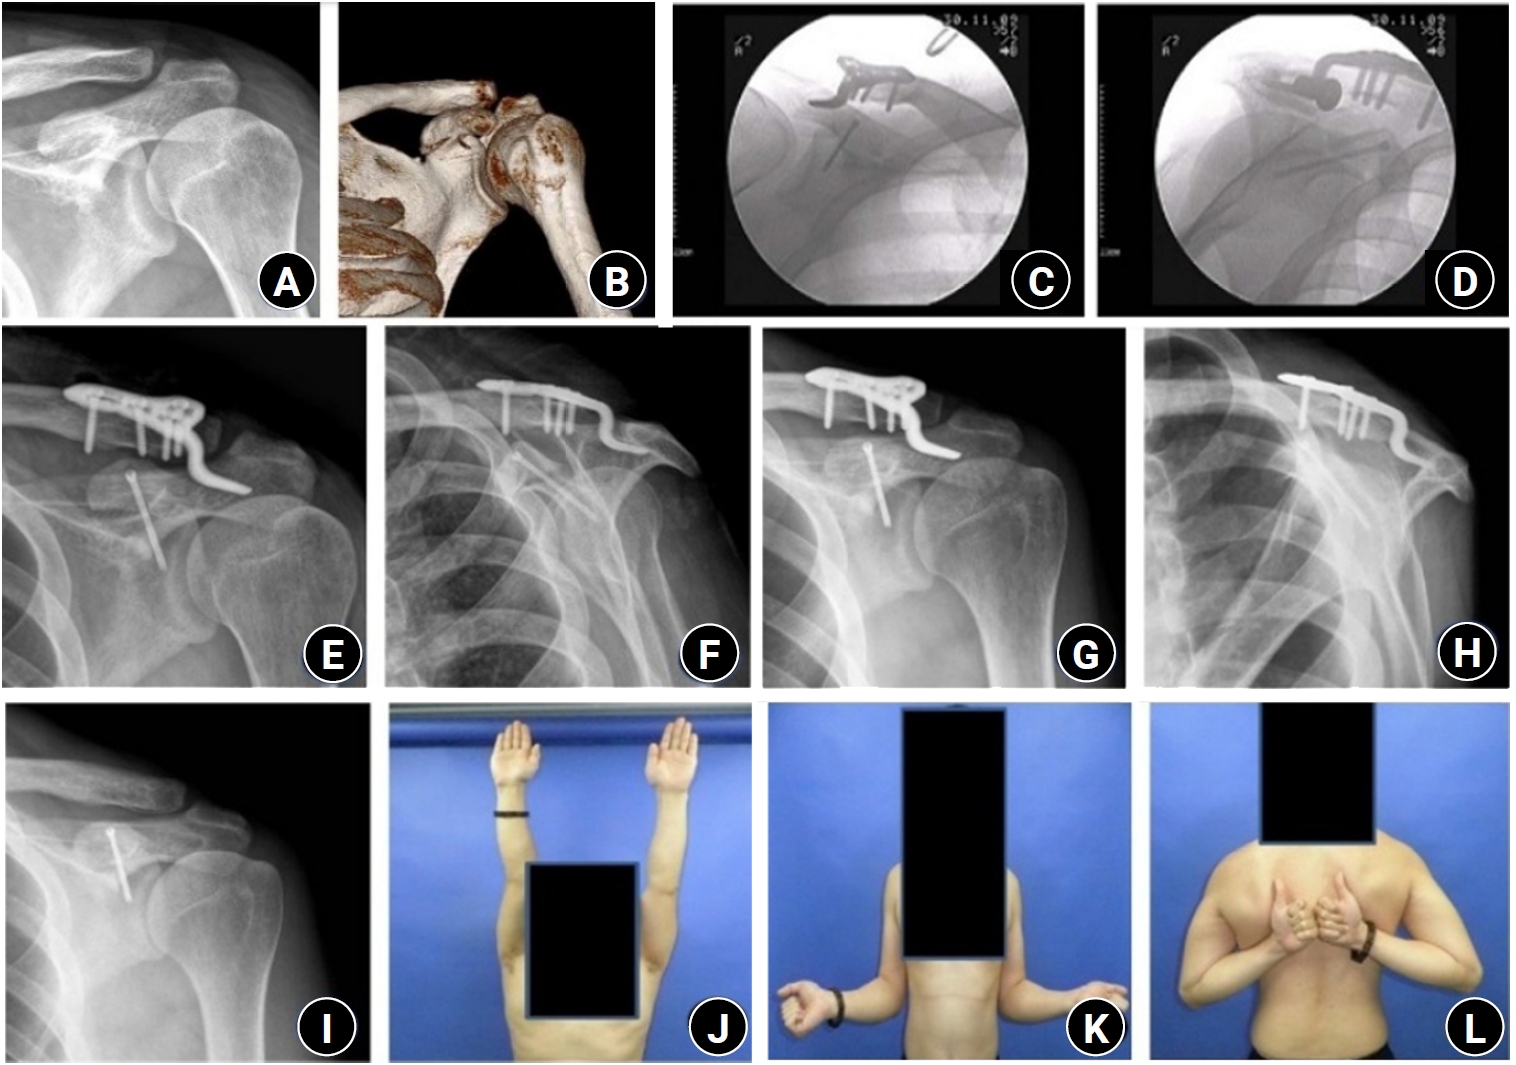

(A, B) Initial shoulder anteroposterior (AP) radiograph and three-dimensional computed tomography images of a 33-year-old male patient show a coracoid process fracture associated with an acromioclavicular joint (ACJ) injury. (C, D) Immediate postoperative C-arm images demonstrate open reduction and internal fixation using a 3.0-mm headless compression screw (HCS) for the coracoid process fracture and a clavicle hook plate for the ACJ injury. (E, F) Immediate postoperative shoulder AP and scapular Y radiographs show fixation using a 3.0-mm HCS for the coracoid process and a clavicle hook plate for the ACJ injury. (G, H) Postoperative 2-month AP and scapular Y radiographs show union of the coracoid process. (I–L) At the final follow-up, the patient demonstrated satisfactory radiographic and clinical outcomes, including full active range of motion.

Fig. 1. (A, B) Initial shoulder anteroposterior (AP) radiograph and three-dimensional computed tomography images of a 33-year-old male patient show a coracoid process fracture associated with an acromioclavicular joint (ACJ) injury. (C, D) Immediate postoperative C-arm images demonstrate open reduction and internal fixation using a 3.0-mm headless compression screw (HCS) for the coracoid process fracture and a clavicle hook plate for the ACJ injury. (E, F) Immediate postoperative shoulder AP and scapular Y radiographs show fixation using a 3.0-mm HCS for the coracoid process and a clavicle hook plate for the ACJ injury. (G, H) Postoperative 2-month AP and scapular Y radiographs show union of the coracoid process. (I–L) At the final follow-up, the patient demonstrated satisfactory radiographic and clinical outcomes, including full active range of motion.

If adequate compression could not be achieved with screw fixation alone, the ACJ was first stabilized with a locking compression hook plate (clavicle hook plate; DePuy Synthes). After sufficient relaxation of the coracoclavicular ligament was ensured, screw fixation was repeated to obtain firm compression at the fracture site. Postoperative radiographs were obtained to assess fracture reduction and fixation (Fig. 1).